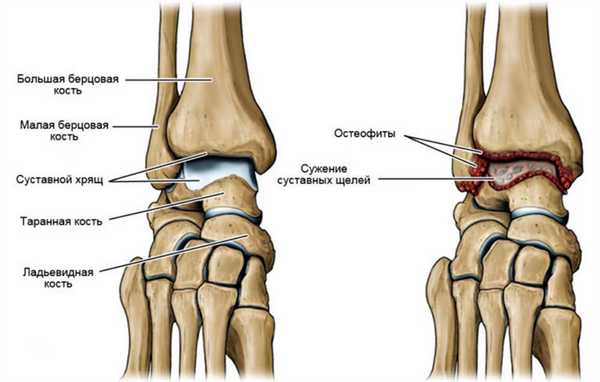

Слева - схематическое изображение строение нармального голеностопного сустава,

Справа - разрушение сустава из-за артроза.

Постепенное истончение хрящевой ткани повышает нагрузку на кости. Со временем, когда хрящ перестает защищать костные ткани, начинается деформация пораженного заболеванием сустава.